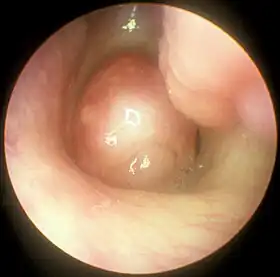

Large choanal polyp seen with nasal endoscopy

Nasal polyps can be seen on physical examination inside of the nose and are often detected during the evaluation of symptoms. On examination, a polyp will appear as a visible mass in the nostril.[6] Some polyps may be seen with anterior rhinoscopy (looking in the nose with a nasal speculum and a light), but frequently, they are farther back in the nose and must be seen by nasal endoscopy.[13] Nasal endoscopy involves passing a small, rigid camera with a light source into the nose. An image is projected onto a screen in the office so the doctor can examine the nasal passages and sinuses in greater detail. The procedure is not generally painful, but the person can be given a spray decongestant and local anesthetic to minimize discomfort.[14]